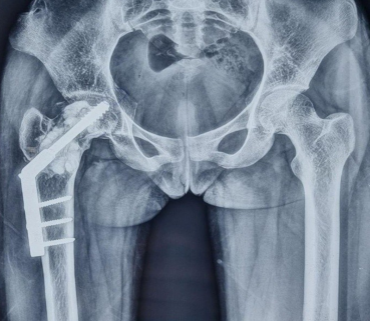

Bilateral Simultaneous Anterior Obturator and Pubic Dislocation of the Hip: A Case Report and Literature Review

Jean de Dieu Tumusifu Manegabe , Gauthier Bahizire Murhula , Alain Kabakuli Namugusha , Paul Budema Munguakonkwa , Georges Kuyigwa Toha , Olivier Cornu

………………………………p.204-208